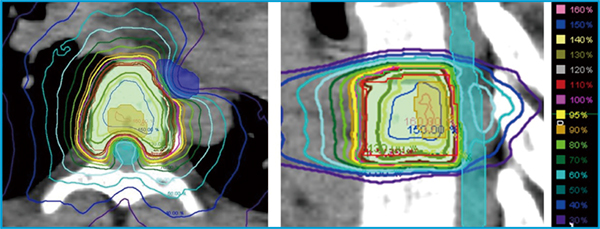

体幹部定位放射線治療(SBRT)は,肺・肝腫瘍に広く用いられてきたが,2020年4月の診療報酬改定で脊椎転移に対しても保険適用となった。それから3年半が経とうとしているが,肺SBRTのように脊椎SBRTが一般的になったかというと,そうではないと感じている。これは,脊椎SBRTではリスク臓器である脊髄と,標的である脊椎が隣接しており,急峻な線量分布を作成し治療を行うため(図1),治療計画から照射までの各工程を高精度に行う「超高精度放射線治療」が必要になるためであると考える。

図1 脊椎SBRTの線量分布

脊椎SBRTでは,リスク臓器である脊髄と,標的である脊椎が隣接しているため,

急峻な線量分布を作成し治療を行う必要がある。